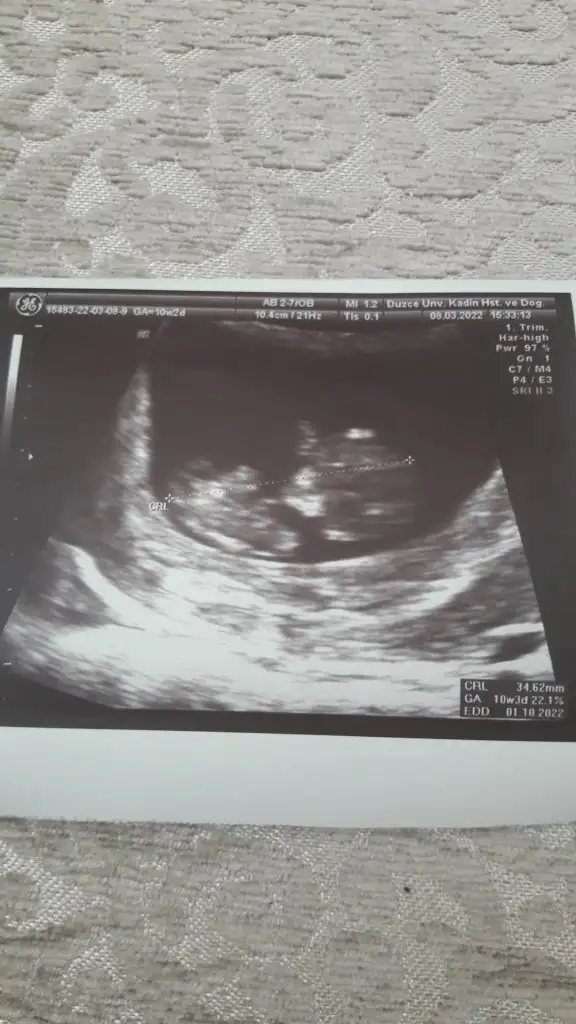

• Screenshot_20220322-105730_Gallery.webp

Screenshot_20220322-105730_Gallery.webp

18,9 KB · Görüntüleme: 264

5 ve 14. haftaya kadar olan ultrason fotolarınızı paylaşın. Vajinadan mı yoksa karından mı çekildiğini ve kaç haftalık olduğunu da mutlaka belirtin.:anneadayı: